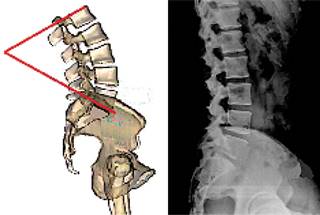

Lordosis lumbar. Es el ángulo que se forma entre la plataforma superior de la primera vértebra lumbar y la plataforma distal de la quinta vértebra lumbar (Figura 18).

La lordosis lumbar normal es muy diferente de individuo a individuo y varía con la edad (disminuye después de la sexta década), el género (las mujeres tienen mayor grado de lordosis que los hombres), la posición y postura, el índice de masa corporal, la etnicidad, el grupo poblacional, el tipo de deportes practicados, la fuerza muscular, la elasticidad, los padecimientos de la columna vertebral por espondilólisis y espondilolistesis ístmica, etcétera.38,39 Aunque hay diversas variables para determinar el grado de angulación lumbar, en general se ha situado como valor normal entre 20o y 45o.39 Es importante recalcar que no hay un estándar universal para hacer mediciones referenciales.